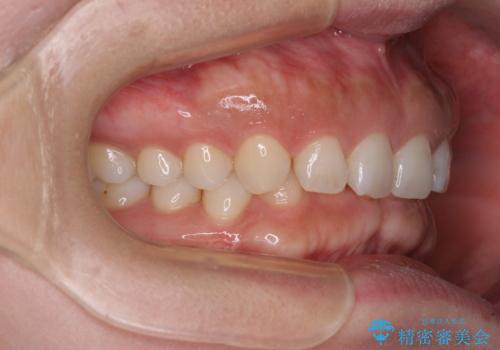

手前に傾斜している奥歯を直立させながら、歯列全体の平面を均一に整えることでディープバイトを改善していくこととしました。

ディープバイトは咬合力が強いことが特徴であり、より良い仕上がりとするために、臼歯部のコントロールを行いやすいワイヤー装置を用いて矯正治療を行うこととしました。

ディープバイトが改善されたことで、食いしばりしかできなかった状態からスムーズな歯ぎしりができるようになりました。